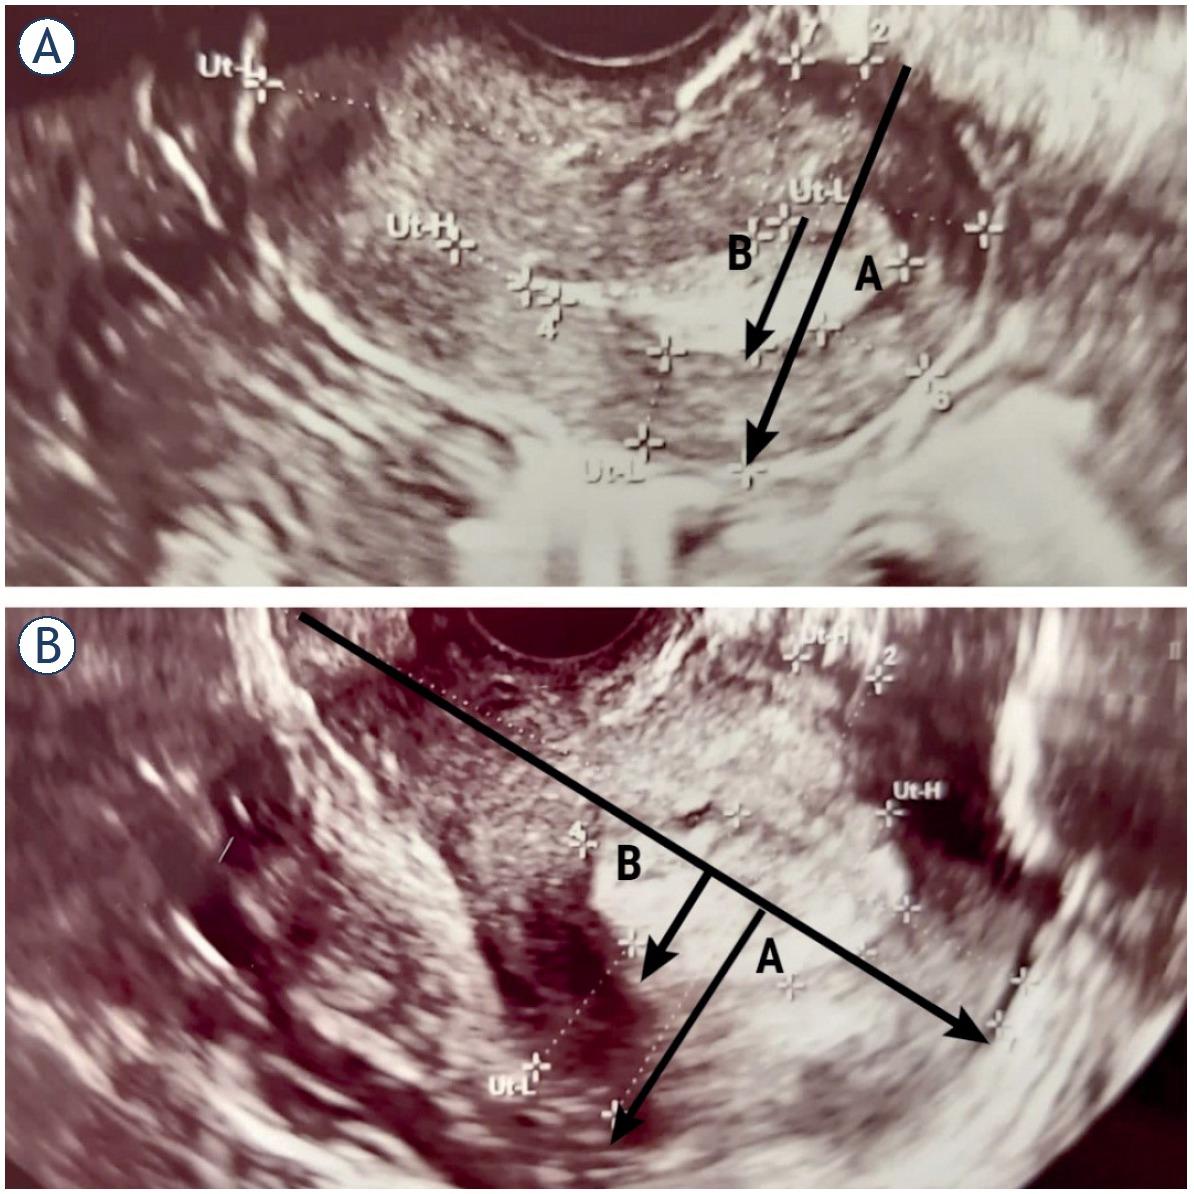

Depth of MI was measured as the ratio between the maximum AP diameter of the endometrial tumor (B) and the uterine AP diameter (A) in sagittal plane, with B/A > 50% indicating deep MI introduced by Karlsson et al. (Figure 1A,Figure 2A).2,5 In other objective method, investigated by Gordon et al., depth of MI was measured as the ratio of the distance between the maximum tumor depth (B) and the total myometrial thickness (A) in sagittal plane, with B/A > 50% indicating deep MI (Figure 1B,Figure 2B).2,5

Assessment of myometrial invasion in patients with transvaginal ultrasonography (TVUS). Stage IA endometrial cancer in a 61-year-old postmenopausal woman, correctly diagnosed by TVUS and MRI. Karlsson’s method indicating infiltration of superficial muscle (29%) (A). Stage IA endometrial cancer in a 53-year-old postmenopausal woman. Gordon’s method indicating infiltration of superficial muscle (35%) (B).